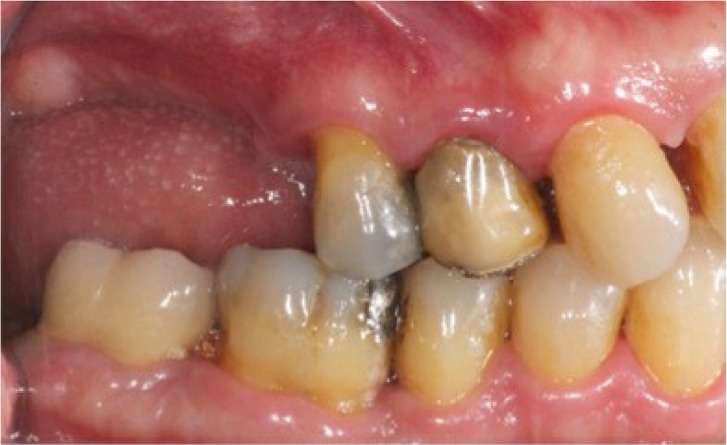

The last visit of follow-up were recorded the plaque index (PI, defined as the presence of plaque/no) bleeding on probing (BOP) using a periodontal probe Hu-Friedy (Chicago, IL, USA) (Figures 6, 7).

Figure 6.

Preoperative intraoral view.

Figure 7.

Postoperative intraoral view.